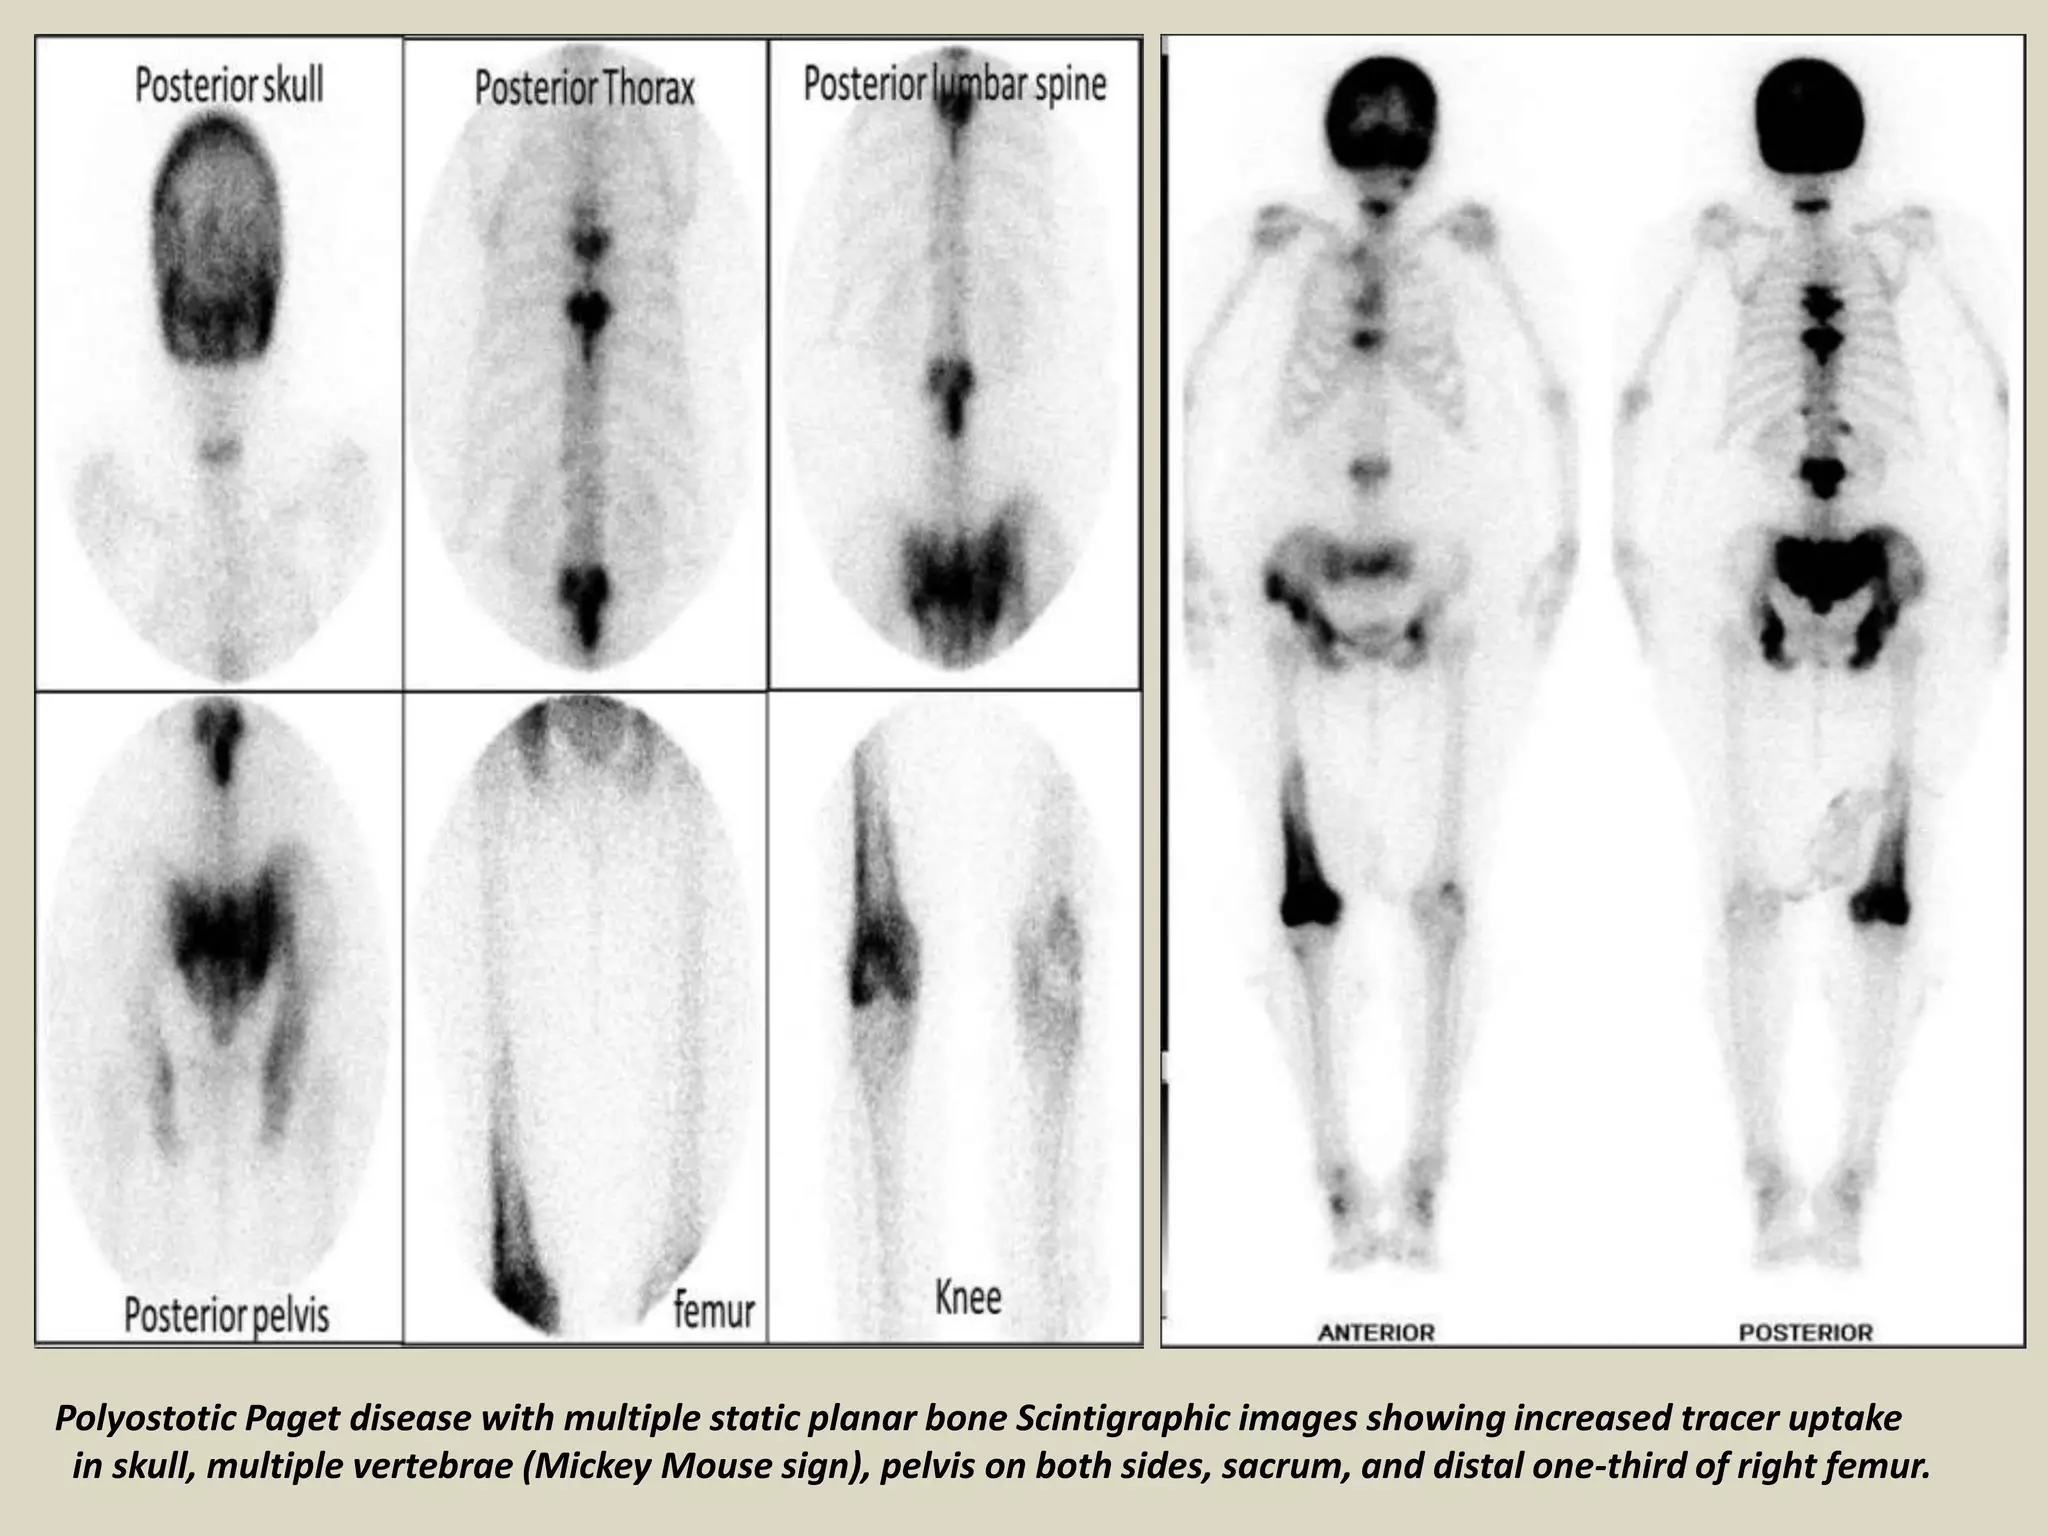

Polyostotic Paget disease with multiple static planar bone Scintigraphic images showing increased tracer uptake

in skull, multiple vertebrae (Mickey Mouse sign), pelvis on both sides, sacrum, and distal one-third of right femur.